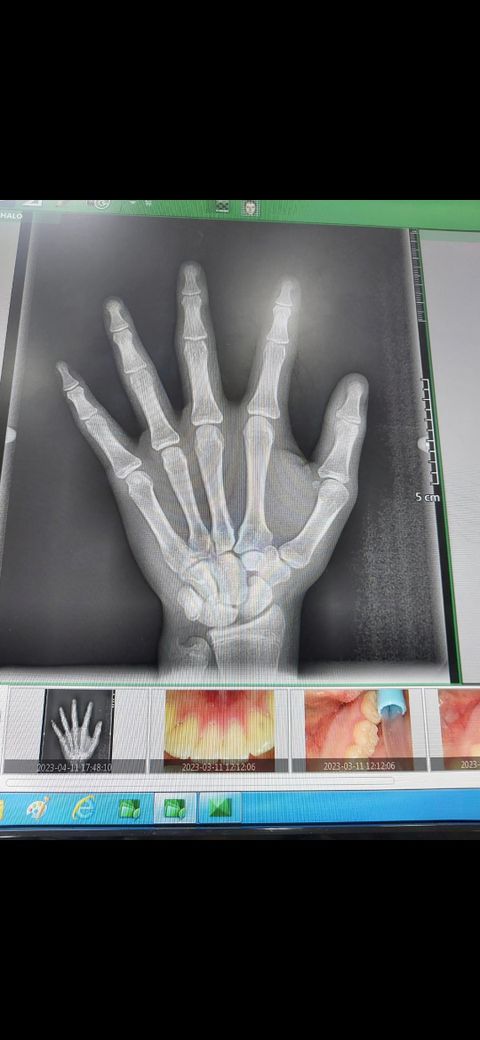

그런데 1년뒤인 2024년 5월에도 키와 몸무게를 측정했는데 키는똑같이 166.3cm가 나왔습니다 그런데 몸무게는 더 늘어서 75kg정도 나왔습니다. 저는 현재 지금 불안하고 떨립니다 제가 여기서 키가 더 안크면 어떻하지라는 생각에 그런데 1년동안 키는 안크고 몸무게만 느는게 너무 불안해서 이런글을 씁니다 제가 이러다 성인까지 키가 안크고 이정도이면 어떻하지라는 생각에 일단 몸에는 다 털이 어느정도 나있고요 그리고 부모님키는.아버지:170cm 어머니:160cm 이정도 입니다 그리고 밑에는 첨부 사진인데요 오른쪽 손 사진 입니다 촬영한 시기는 2023년 4월 11일 오후6시6분정도 입니다. 진짜 진지하게 답변해주시면 진심으로 감사하겠습니다 감사합니다. 그리고 생년월일은 2008년 9월 5일 입니다.

이거는 2023년 4월 11일 오후6시에 찍은 사진 입니다.

약 1년전 촬영한 성장판 검사에서 성장판이 거의 닫힌 상태이고

말씀대로 최근 1년동안 키가 거의 자라지 않은 것이 확실하다면,

성장이 거의 마무리 되었을 가능성을 무시하기는 어렵습니다.